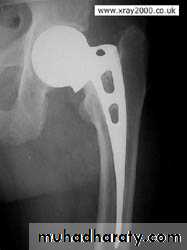

ELDERLY PEOPLE

5.Austen Moore.6.Total hip replacement.